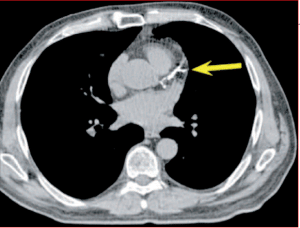

. attention mesure faussée en cas :

• de tachycardie (possible administration de beta-bloquer)

• si artères calcifiées

• artères distales